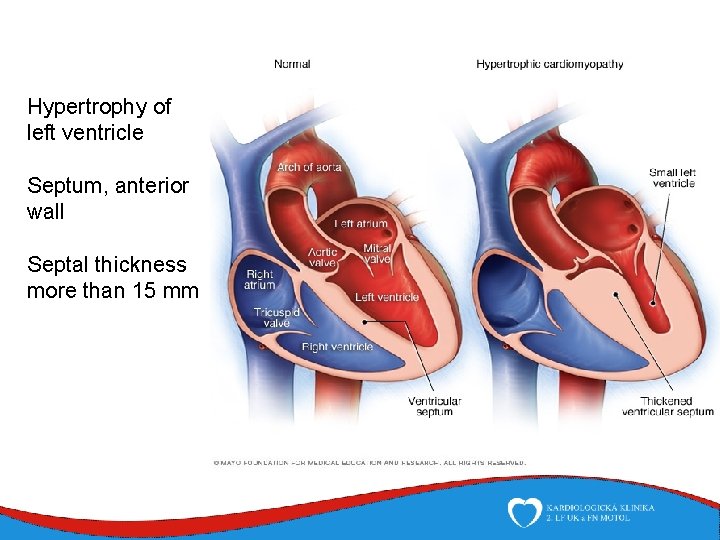

Hypertrophy of left ventricle Septum, anterior wall Septal thickness more than 15 mm